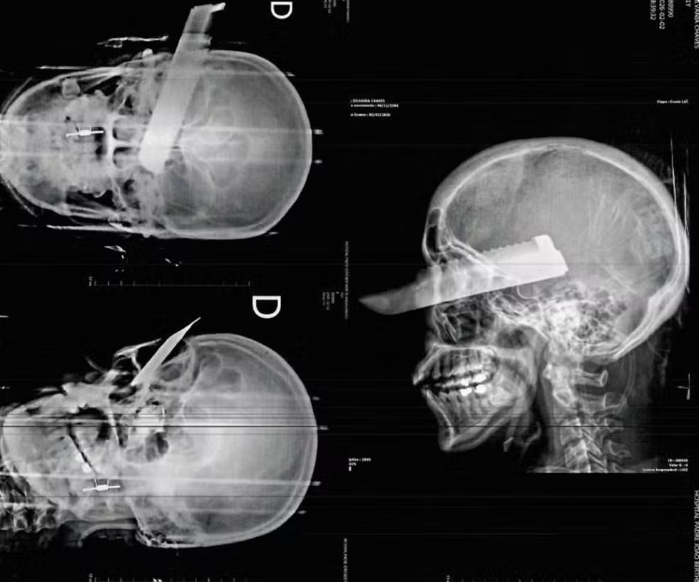

De acordo com informações da Polícia Civil, a vítima foi agredida dentro da própria casa pelo homem, de 26 anos, e atingida por um golpe de faca no rosto enquanto tentava fugir da violência. Mesmo ferida, ela conseguiu escapar, pedir ajuda a vizinhos e acionar o socorro.

O Corpo de Bombeiros prestou atendimento no local e encaminhou a mulher ao Hospital Regional do Oeste, em Chapecó. Ela apresentava hematomas no rosto, no braço e na perna esquerda, além de uma lesão grave no olho direito. Até o momento, não há atualização oficial sobre o estado de saúde da vítima.

Foto: Divulgação/Polícia Civil de Santa Catarina